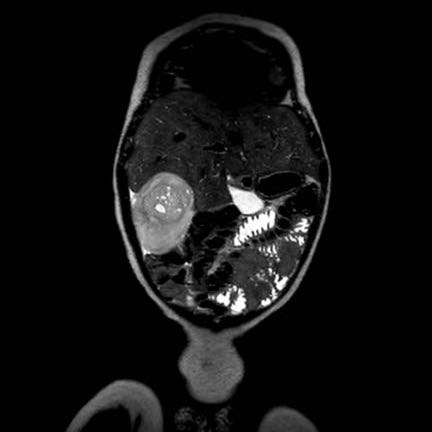

Các hình ảnh này thuộc về bé gái một tuổi.

Trên siêu âm, ghi nhận một khối u đa nang với tín hiệu tưới máu ở các vách ngăn.

Hình ảnh chuỗi xung T2W cho thấy rõ hơn phạm vi của tổn thương. Có thể quan sát thấy phần mô thận bình thường còn lại ở cực dưới, giúp phân biệt tổn thương này với thận loạn sản đa nang.

Khối u này được chẩn đoán là u thận dạng nang, và bệnh nhân đã được phẫu thuật cắt thận phải.